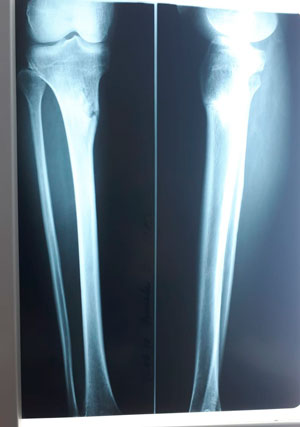

в процессе работы

IMG_2287-09-04-19-08-26.JPG

IMG_2289-09-04-19-08-26.JPG

IMG_2288-09-04-19-08-26.JPG